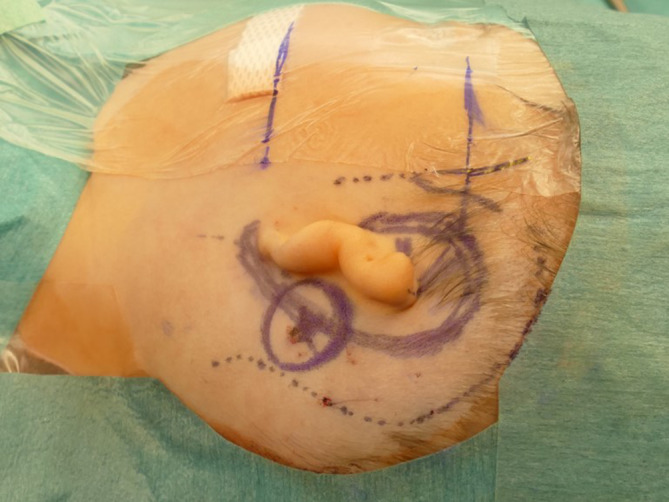

Fig. 2.

Landmarks for transferring the preoperatively determined implant position into the surgical field. Suitable landmarks include the mastoid tip, the anterior wall of the external ear canal or its remnants, the lateral orbital rim (not shown here), or the temporomandibular joint [17]. During planning, bone thickness is measured in the area where the self-drilling cortical screws will be placed to fix the bone conduction-floating mass transducer [33]